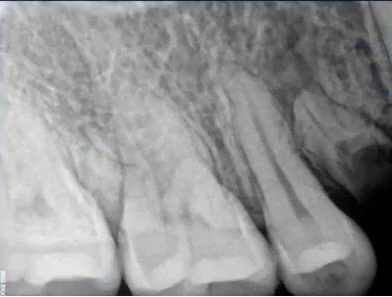

临床检查时发现14残根,牙龈红肿。曲面断层片上由于前磨牙转角问题,看不到残根,无法明确到底有没有残根,无法通过曲面断层片进行确诊或评估。

曲面断层片怎么看口腔精读 | 一次性教你看懂曲面断层片!_https://www.jmylbn.com_新闻资讯_第22张

这时需要加拍根尖片,很明显能看到残根。这就说明,有曲面断层片也不能排除情况。

曲面断层片怎么看口腔精读 | 一次性教你看懂曲面断层片!_https://www.jmylbn.com_新闻资讯_第23张

临床检查45叩诊(+),牙颌面见畸形中央尖。加拍根尖片可看到,右下5根方有低密度影,并且右下5的牙根较短小,和曲面断层片上显示的大小不同,所以右下5是舌向倾斜的牙齿。